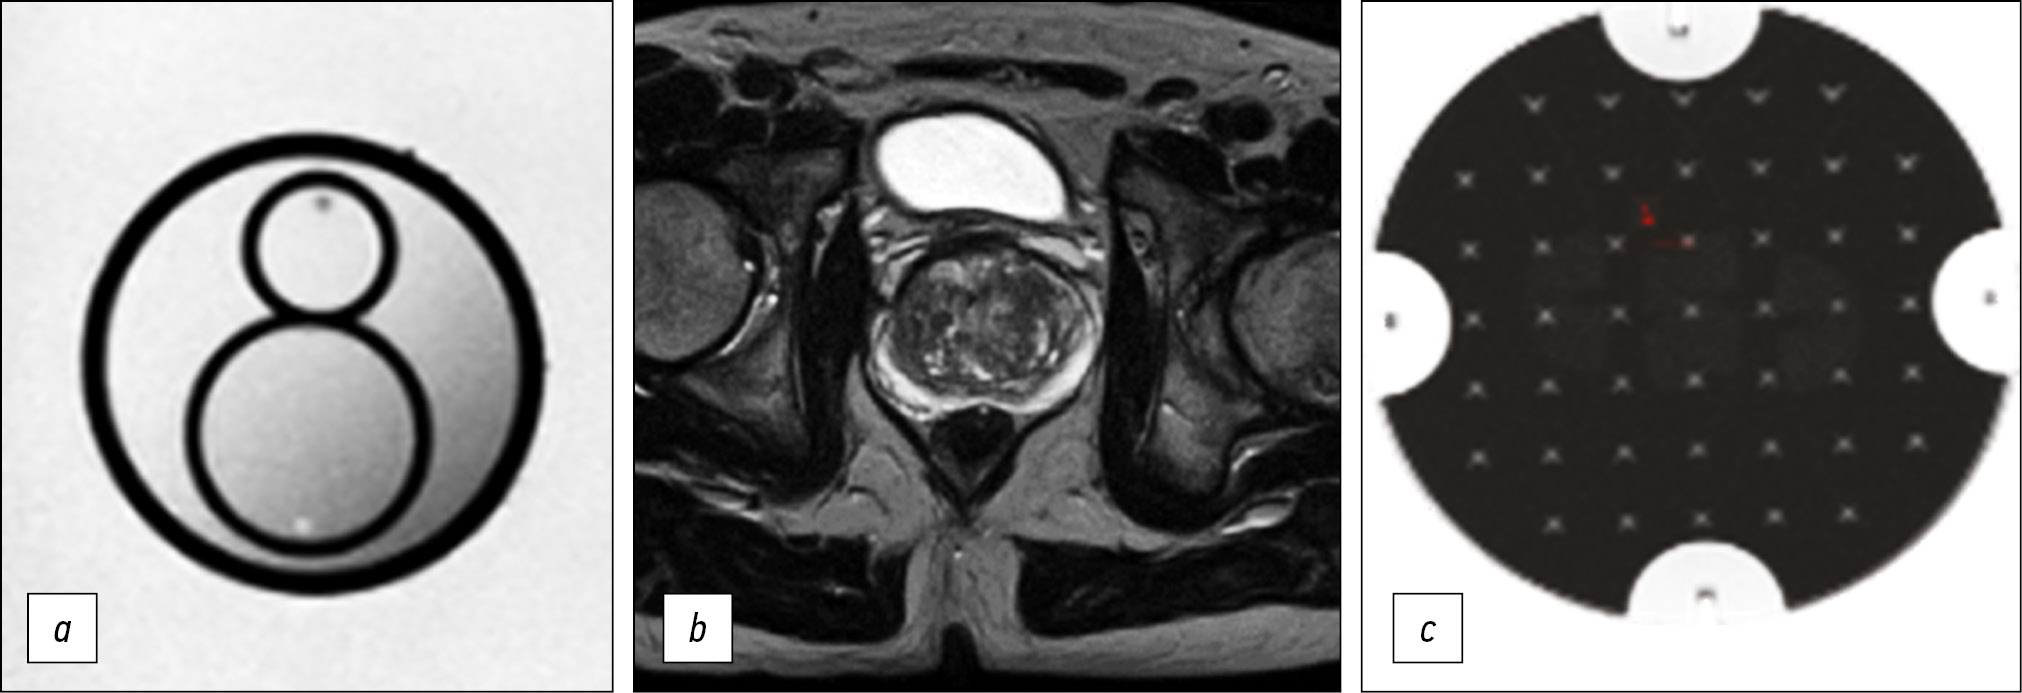

Fig. 4. Medical organization 3 (MO 3). In the peripheral zone on the left, a hypointense lesion on T2-WI and ICD map is defined (arrows): a) T2-WI, axial projection (TR 5082, TE 75, FOV 40×30 cm, Matrix 512×256); b, c) DWI and ICD (TR 8841, TE 100, FOV 30×30 cm, Matrix 128×128).

Note. Here and in Figures 3–5: T2-WI, T2 weighted images; DWI, diffusion-weighted images; MDC, measured diffusion coefficient; TR, repetition time; TE, echo time; FOV, field of view; Matrix is a matrix.

Thus, in all presented HO MHD, the requirements recommended by PI-RADS v2.1 for the presence of T2-WI in the axial and at least one additional (sagittal and/or coronal) views were met. In addition, it should be noted that the recommended layer thickness for T2-WI in the axial view should be no more than 3 mm, while in HO 2 and HO 3, it is 4 mm (Figures 3 and 4). The same is true for HO 1, where the DWI slice thickness is 5 mm with the recommended 4 mm or less (Figure 2). An important factor is the field of view; according to PI-RADS v2.1, field of view (FOV) values for T2-WI should be 12–20 cm, while in HO 1 and HO 3, the field of view is much larger (30 × 35 cm and 40 × 30 cm, respectively) (Figures 2 and 4). According to PI-RADS v2.1, the recommended field of view for DWI is 16–22 cm, although none of the three HOs adhere to this standard. The fact of the variability of the FOV values and the section slice thickness inevitably affects the resolution and, as a result, the ability to detect lesions.